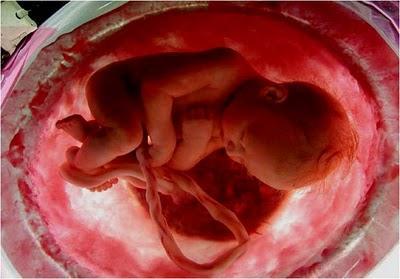

YA COMPLETÓ NUEVE MESES Y ESTÁ LISTO PARA NACER.EN 40 SEMANAS, LO QUE ERA APENAS UNA SIMIENTE,SE TRANSFORMÓ EN UN SER HUMANO.

EL MILAGRO DE LA FORMACIÓN DE LA VIDA HUMANAEN EL INTERIOR DEL CUERPO MATERNO ESTÁ A PUNTO DE QUEDAR TERMINADO.

EN POCOS DÍAS LOS PULMONES Y LA PLACENTA SE ENCARGARÁN DE DAR LA SEÑAL DE QUE HA LLEGADO LA HORA DEL PARTO.

EL BEBÉ DUERME, TRANQUILO,EN EL VIENTRE DE SU MADRE.

DENTRO DE POCO ABANDONARÁ LA PLACIDEZ DE SU "CASA" PARA VIVIRLA PRIMERA AUTONOMÍA DE SU VIDA: EL NACIMIENTO.

SÍ, PORQUE EL PARTO NO SOLO PUEDE SER DOLOROSO PARA LA MADRE.TAMBIÉN PUEDE SER TRAUMÁTICOY "ESTRESANTE" PARA EL BEBÉ.

Y ES ASÍ COMO ACONTECEEL MILAGRO DE LA VIDA